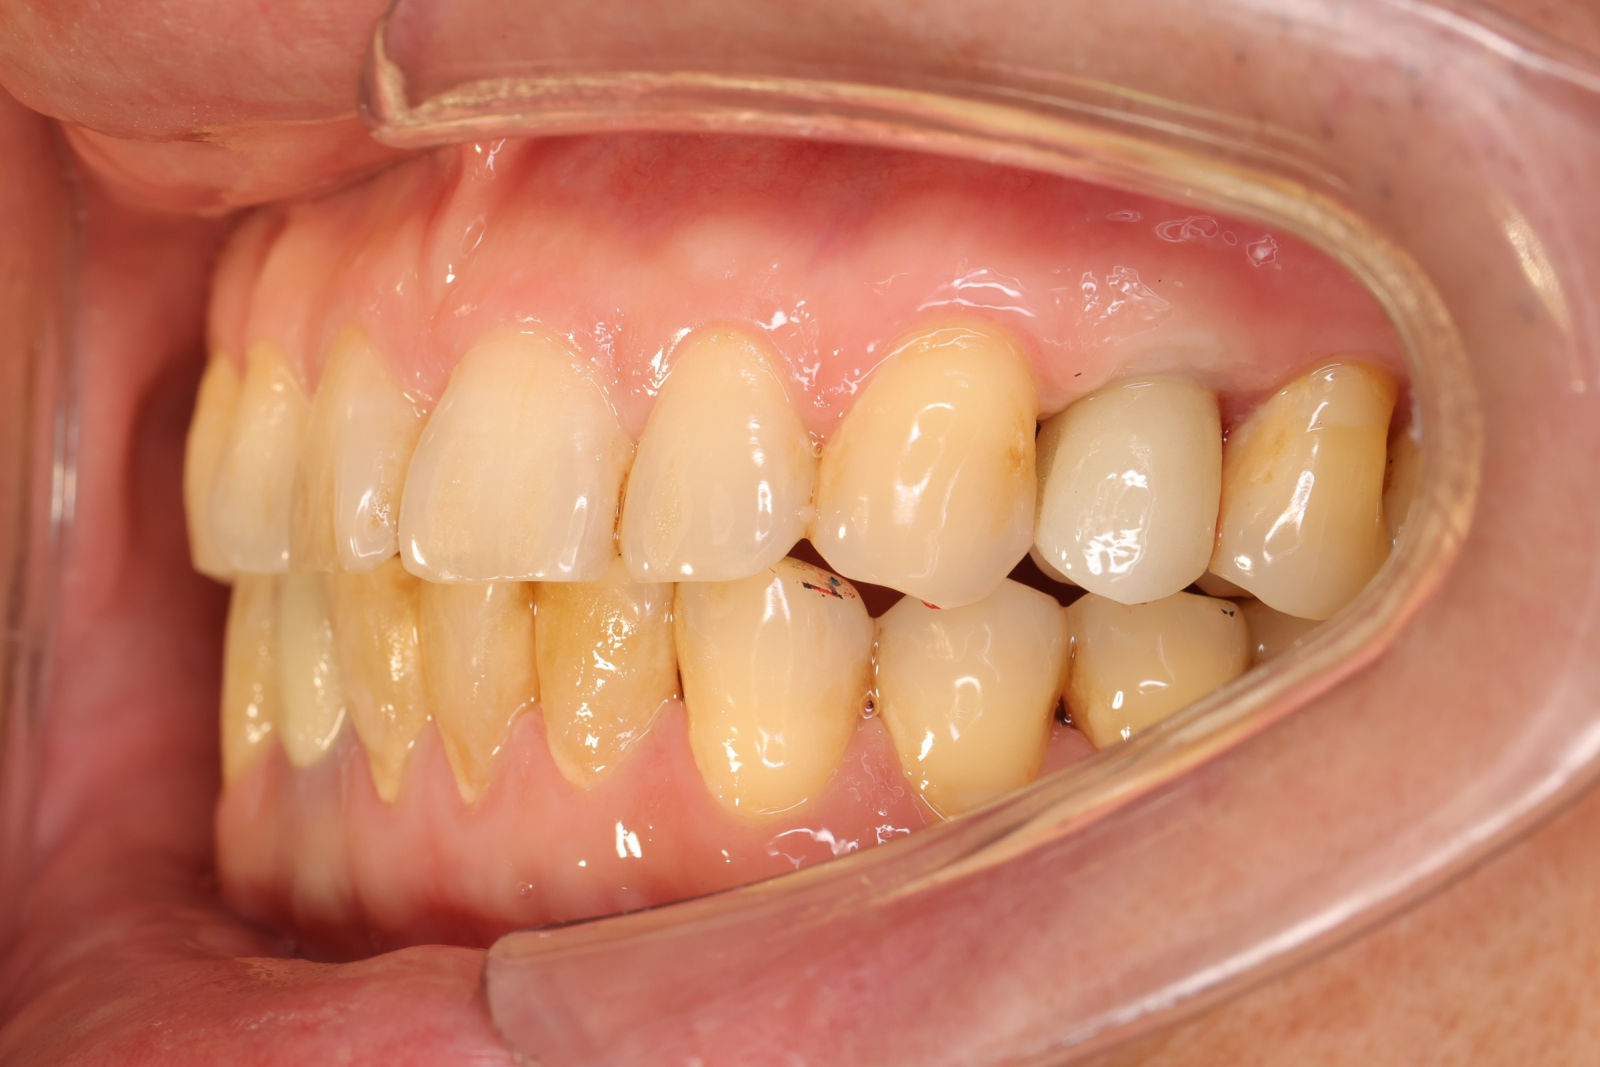

【 案 例 一 】

- 手術過程,在植入植體前先用導板定位,確認植牙位置及角度。

- 植牙當下不用劃開傷口無須縫合,鎖上癒合帽即可,也不需縫合傷口

待3.4個月後裝上全陶瓷牙冠完成植牙療程。整個療程過程輕鬆。